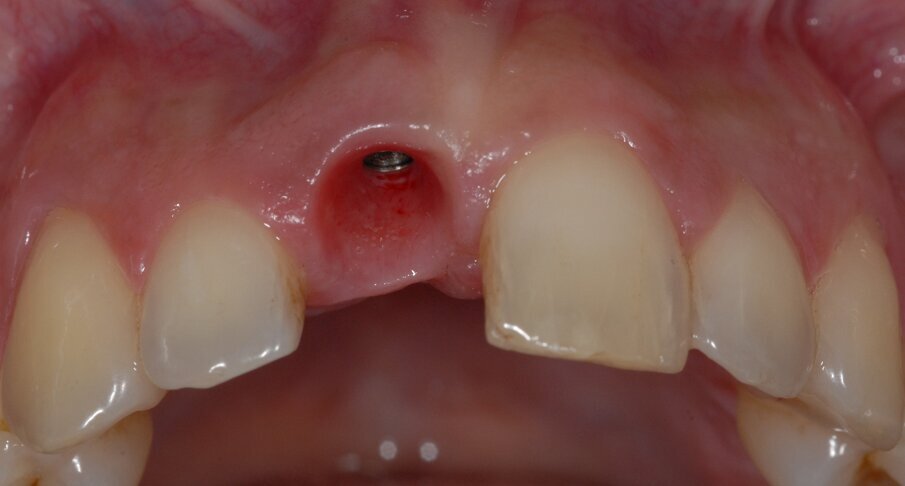

Infine, il foro di accesso della vite è stato riempito con del teflon e ricoperto con materiale da riempimento temporaneo (Telio inlay, Ivoclar, Italia). È stata, quindi, controllata l’occlusione e sono stati rimossi i contatti sia in occlusione statica che dinamica (Fig. 4).

Alla paziente è stato chiesto di evitare di masticare sull’area trattata per 3 mesi e di evitare di lavarsi i denti per le prime 2 settimane. È stato prescritto un risciacquo con clorexidina allo 0,12% (Eburos, Dentsply) per 2 settimane. Successivamente, sono stati consentiti lo spazzolino convenzionale e il filo interdentale. La paziente ha mantenuto il provvisorio per 12 mesi, quindi è stata presa un’impronta, secondo la metodica di Hinds16 (Fig. 5). È stata, quindi, realizzata e avvitata sull’impianto una corona in zirconia-ceramica con moncone individualizzato (Figg. 6, 7).

Fig. 5 - I tessuti perimplantari a un anno dall’intervento sono molto belli sia per forma che per tono e stato di salute. Le papille sono competenti e la parabola è simmetrica a quella dell’elemento adiacente. La bozza radicolare è molto ben conservata (Root Bump Preservation RBP).